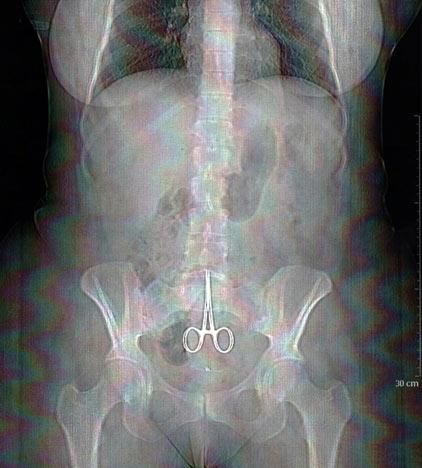

Foto del 13 de febrero de 2011 en Lyon, Francia, que muestra un par de pinzas quirúrgicas en el abdomen Anne, una mujer que se quejó de dolores tras seis meses de haber recibido una cirugía.